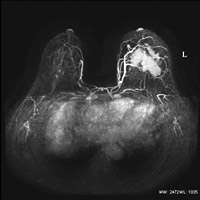

造影剤を用いた乳房検査

造影剤を使用しない尿路検査

造影剤を使用しない腹部血管検査